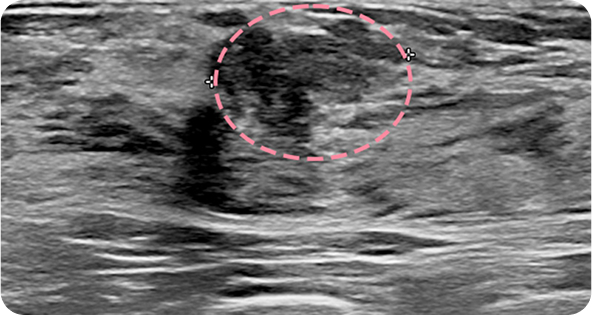

영상 특화 전문의니까

초음파 보면서

맘모톰도 안전하게

맘모톰시술 후 병리조직검사 결과 상피내암(조기 유방암) 초기로 진단되어 항암치료 없이 간단한 수술로 치료가 가능했습니다. 눈에 잘 띄지 않는 작은 병변까지 확인할 수 있었던 건, 맘모톰의 정밀한 조직검사 기능과 전문의의 정확한 판독이 있었기 때문입니다.

양성 종양은 여러 개가 동시에 생겨나기도 합니다. 정상적인 유방 조직 보전에 신경 쓰며 맘모톰 시술을 섬세히 진행했고, 6개월 뒤 추적 관찰을 위한 유방초음파에서 종양이 깨끗이 제거된 것을 확인했습니다. 일부 반흔 조직은 자연스럽게 호전될 것으로 보여 좋은 예후가 기대되었습니다.